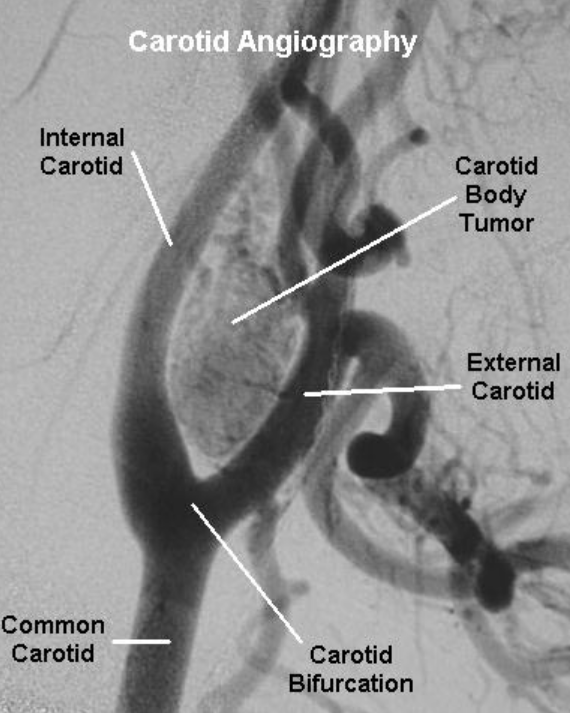

A carotid body tumor is a rare, usually benign (non-cancerous) growth that develops at the bifurcation of the carotid artery—where the artery splits in the neck to supply blood to the brain. Though slow-growing and typically painless, the tumor’s close location to major blood vessels and nerves means it must be handled with expert precision.

- CT angiography or MRI/MRA to map the anatomy and evaluate the relationship between the tumor, carotid arteries, and surrounding structures